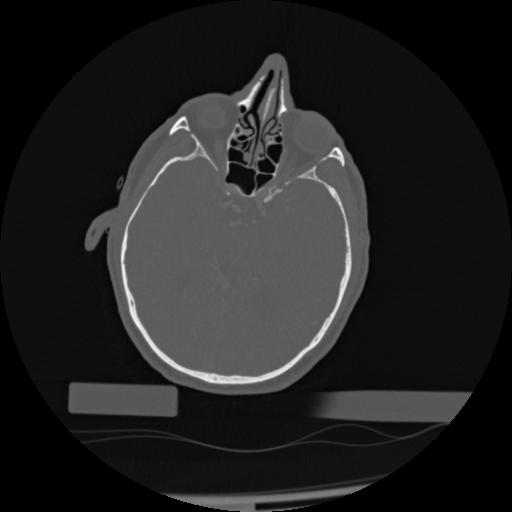

22 ANGIO,CE,Vol,0.5,ANGIO,,